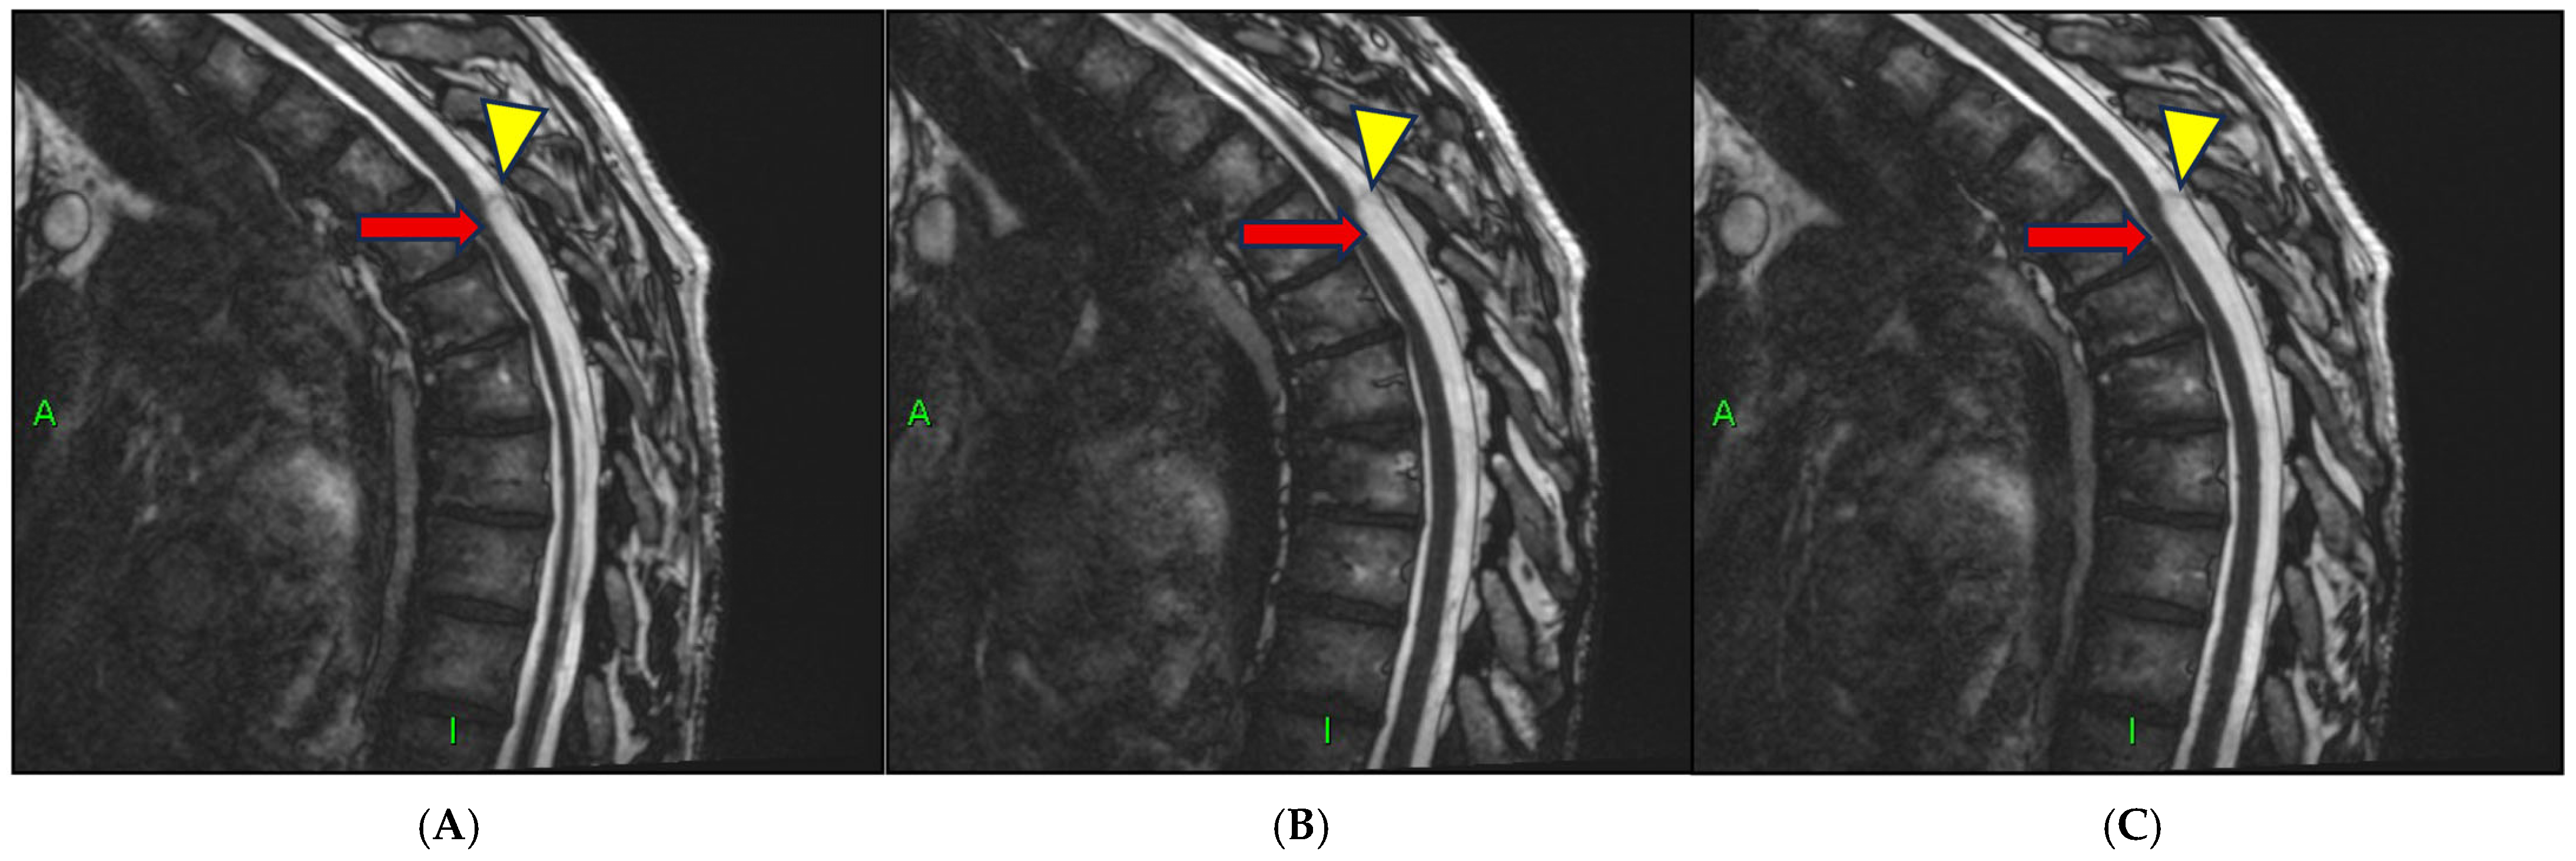

- Chang, H.S.; Nagai, A.; Oya, S.; Matsui, T. Dorsal spinal arachnoid web diagnosed with the quantitative measurement of cerebrospinal fluid flow on magnetic resonance imaging. J. Neurosurg. Spine 2014, 20, 227–233. [Google Scholar] [PubMed]

- Grewal, S.S.; Pirris, S.M.; Vibhute, P.G.; Gupta, V. Identification of arachnoid web with a relatively novel magnetic resonance imaging technique. Spine J. 2015, 15, 554–555. [Google Scholar] [CrossRef] [PubMed]

- Nada, A.; Mahdi, E.; Mahmoud, E.; Cousins, J.; Ahsan, H.; Leiva-Salinas, C. Multi-modality imaging evaluation of the dorsal arachnoid web. Neuroradiol. J. 2020, 33, 508–516. [Google Scholar] [CrossRef]

- Brasil, P.; Pereira, L.; Távora, D.; Camara, A.; Filho, C.M.; Coimbra, P. Imaging findings in dorsal thoracic arachnoid web and the differential diagnosis of “Scalpel Sign”. Neurographics 2020, 10, 96–102. [Google Scholar] [CrossRef]

- Mukherjee, S.; Reardon, M.A.; Raghavan, P. Dorsal thoracic arachnoid web: Another intradural entity with ventral cord displacement. RadioGraphics 2015, 35, 297–298. [Google Scholar] [CrossRef] [PubMed]